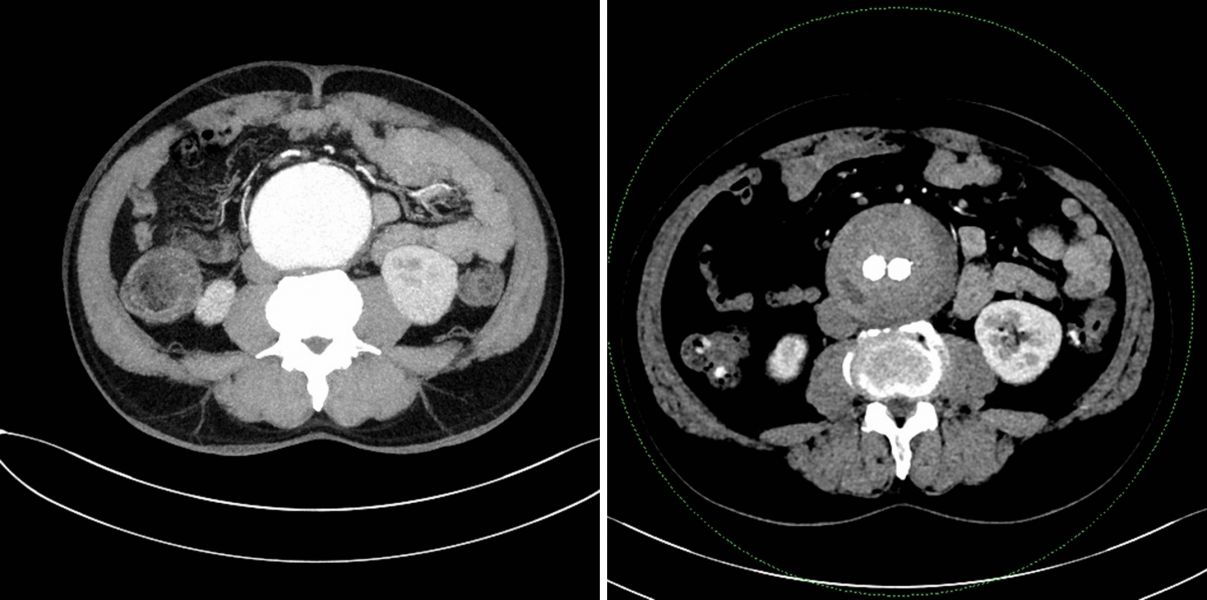

通过增强CT资料显示:患者的瘤体总长度超过20cm,最大直径达7.5cm,瘤颈短且极度扭曲,扭曲度超过60°,而且双侧髂总动脉、髂内动脉均受累及,需要同时处理,手术难度极高。

术前术后CT横断面对比